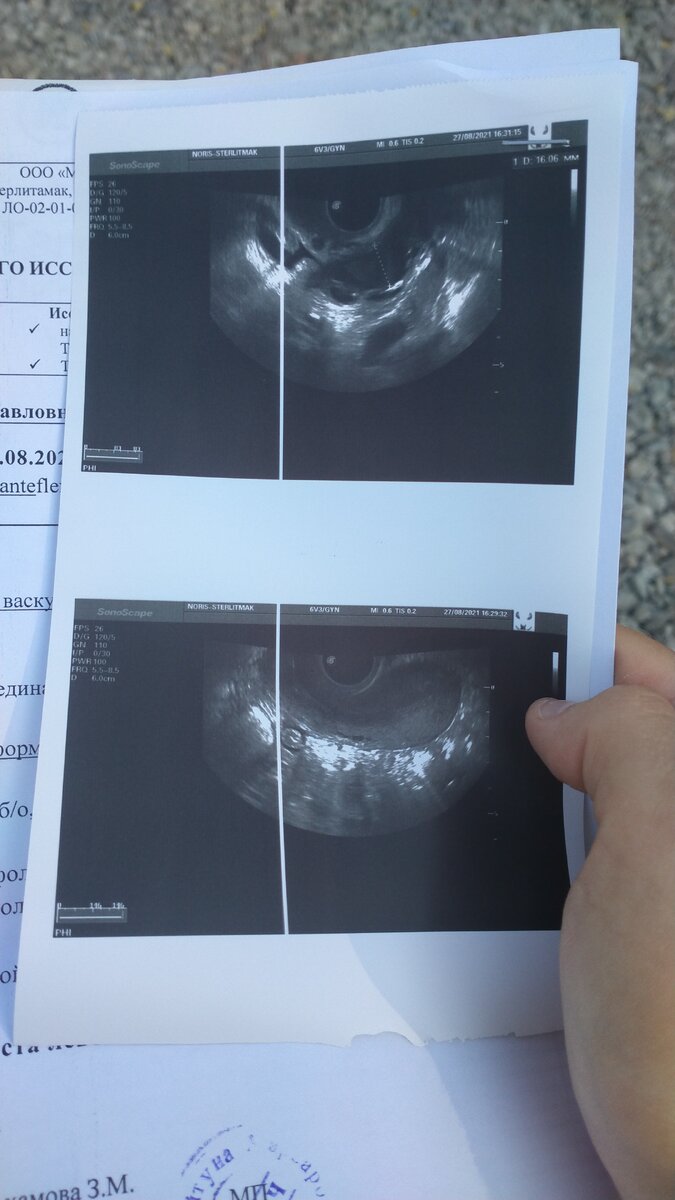

Вот и я доигралась до того, что заработала себе проблем со здоровьем. Врач УЗИ сказала, что у меня прибавилась ещё одна проблема. Я серьезно подумала, что неправильная беременность. Но...

У вас доброкачественная опухоль-киста. Функциональная. Может, через два месяца пройти, а может и нет.

Да, вот такое у меня прибавление: ещё одна проблема. Во время критических дней, я лежала еле живая.

Адская боль внизу живота. Спазм. Таблетка обезболивающего. Не помогает. Два часа я лежала не шевелясь. Поднялась температура 38. Знобило. И весь следующий день. Гинеколог сказала, что у меня по анализам видно, что в организме воспаление.